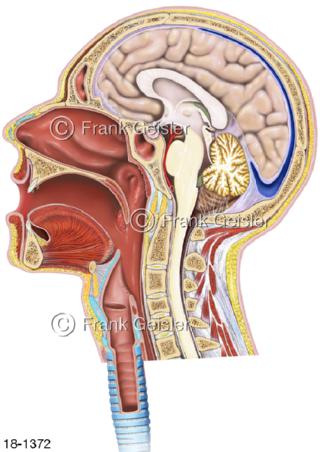

18-1372 Notfall Kopf mit Nasen-Rachen-Raum